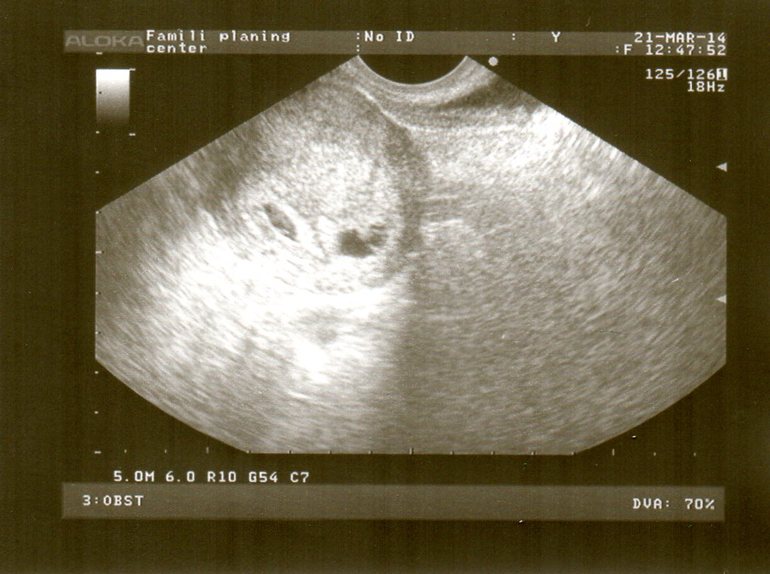

Всё о нашей беременностиДевчули привет! Сегодня ездила на второе УЗИ. Еле дождалась!!! Наконец то увидела своих малявочек!!! Первый: 20х10х16 с желт.мешком диаметр 5. эмбрион КТР 5мм СБ+. Второй: 12х7х15 с желт.мешком диаметр 4 мм эмбрион КТР 4 мм СБ+. Единственное мне очень не понравилось, написали гипертонус по передней стенке. т.е. угроза невынашивания... Врача спросила, она ме ответил что это в принципе не страшно, добавить папаверин + ношпа....

А вот, собственно, и мои малявочки!!!